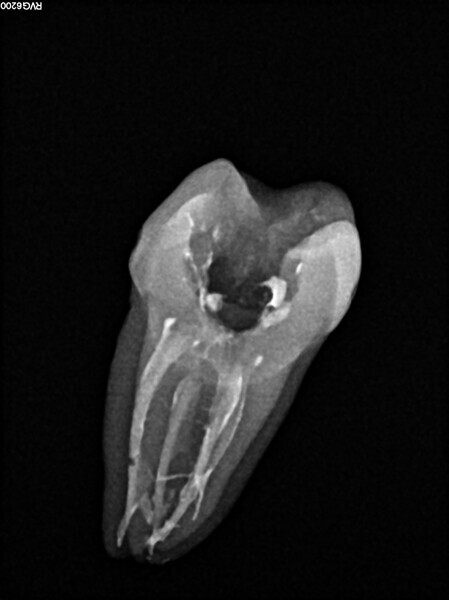

Post-op radiograph of a mandibular molar. (All Images: Bartłomiej Karaś)

A 25-year-old female patient presented to the office owing to constant pain related to the mandibular left first molar. Pulp necrosis was diagnosed. After the emergency appointment, the patient was referred for complete treatment. The tooth was treated in the same manner as described in the previous paragraphs. After creation of the access cavity, the orifices were located. In the root chamber, the orifices of the MB, mesiolingual, DB, distomesial and distolingual canals were present. After pre-flaring and preparation of the middle third, the LPE enhanced irrigation protocol with the SkyPulse laser was performed. After the irrigation protocol in the mesial root, the irrigants started to flow between lingual and buccal canals. Such an observation suggested to the operator that some space in the isthmus had been created. It is worth mentioning that at this stage apical enlargement was not performed. Final preparation of all five canals was performed with the reciprocating file, and the final irrigation protocol was performed as in the previous case. The radiograph clearly revealed that the isthmus space was filled with the sealer. The radiograph and CBCT image revealed that there were four portals of exit in the mesial root.